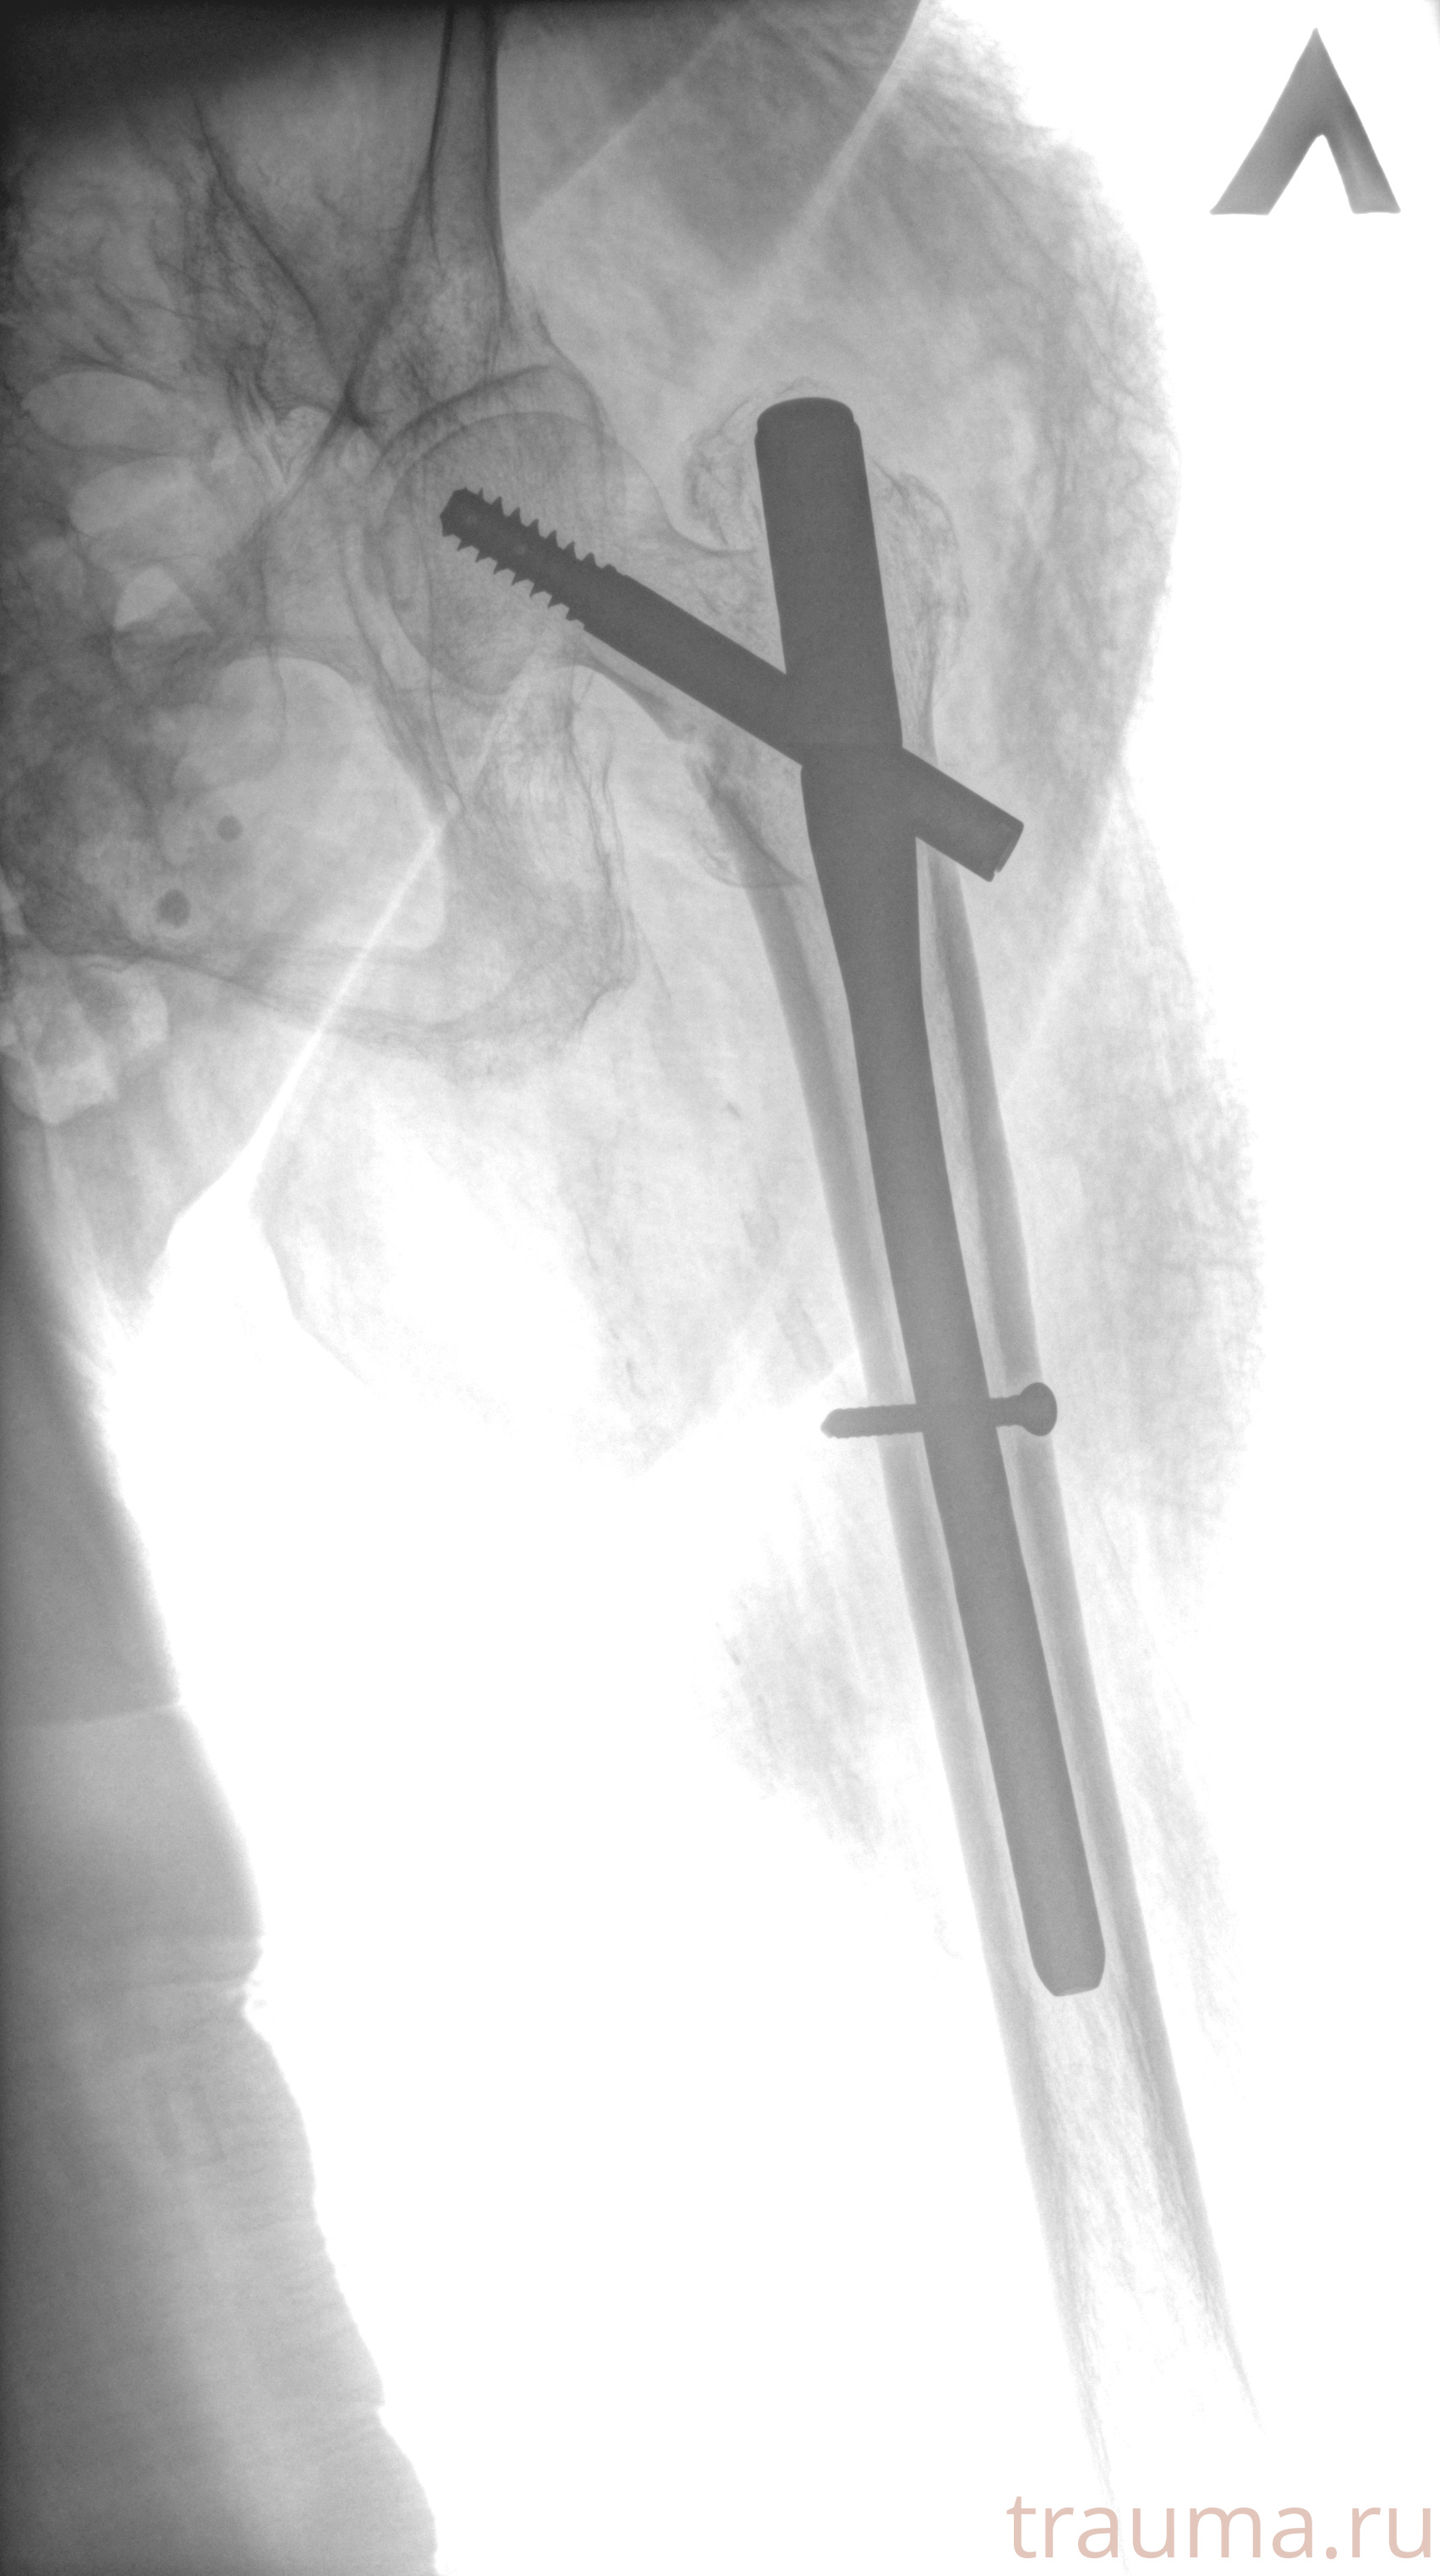

Рентгенограммы

Рентген на дому: по вашему адресу приезжает врач-рентгенолог, травматолог-ортопед с мобильным рентгеновским аппаратом, проводит диагностику травмы или заболевания, делает необходимые рентгенограммы, дает рекомендации по дальнейшему лечению. Получить качественные снимки в домашних условиях возможно благодаря уникальной методике, разработанной МосРентген Центром для института  Склифосовского